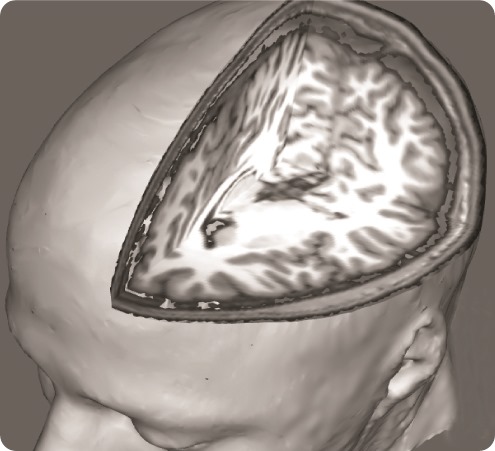

In order to address this question, we used a brain imaging technique called ‘functional Magnetic Resonance Imaging’, which allows us to examine how brain activity changes in association with certain states or tasks.

He is particularly interested in the study of brain alterations associated with chronic pain conditions, which he investigates using a variety of neuroimaging techniques, including functional Magnetic Resonance Imaging, Arterial Spin Labeling and Positron Emission Tomography.